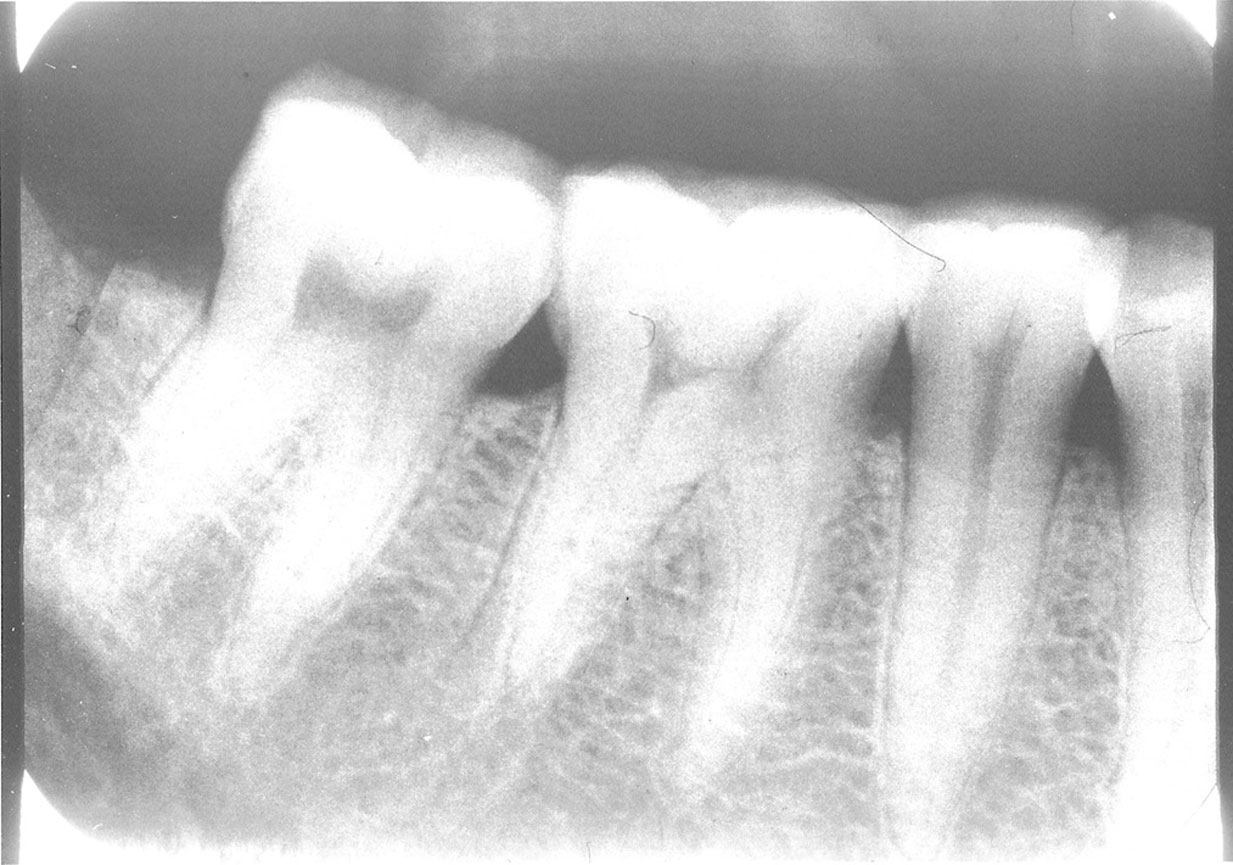

Foreshortening

Description: Foreshortening occurs when the central ray from the tubehead is too high, making the vertical beam angulation too steep. The image appears shortened particularly at the portions of the teeth that were closest to the beam (Figure 4).

Differential Diagnosis: Visible shortening of the teeth, with somewhat wider appearance of objects closest to the x-ray head. The incisal or cuspal edge may be partially missing. The posterior teeth may show a greater distance between the buccal and lingual cusps (Figure 5).

Consequences: The image may still be acceptable, despite the error. If the foreshortening interferes with the film’s diagnostic quality, a retake is necessary.

Remedy: The operator should review technical procedures regarding vertical angulation in relation to Paralleling technique or Bisect-the-Angle technique and repeat the film. The operator should decrease the vertical angulation in order to correct foreshortening of an image.

Figure 4. Foreshortening.

Figure 4

Figure 5. Example showing distance between cusps.

Figure 5